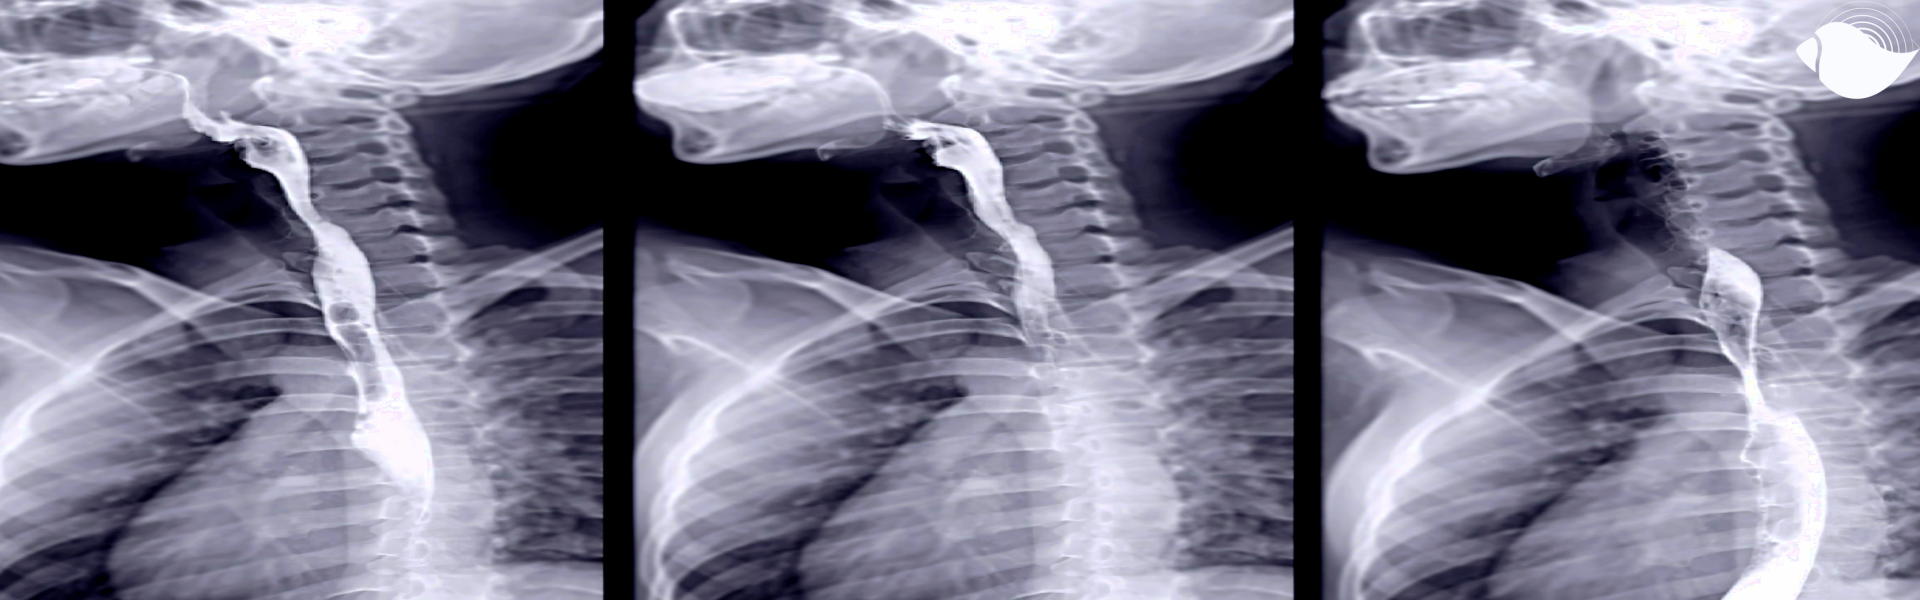

Hacemos estudios de rayos x de rutina y estudios especiales con medio de contraste.

¿Para qué sirve una serie esofagogastroduodenal?